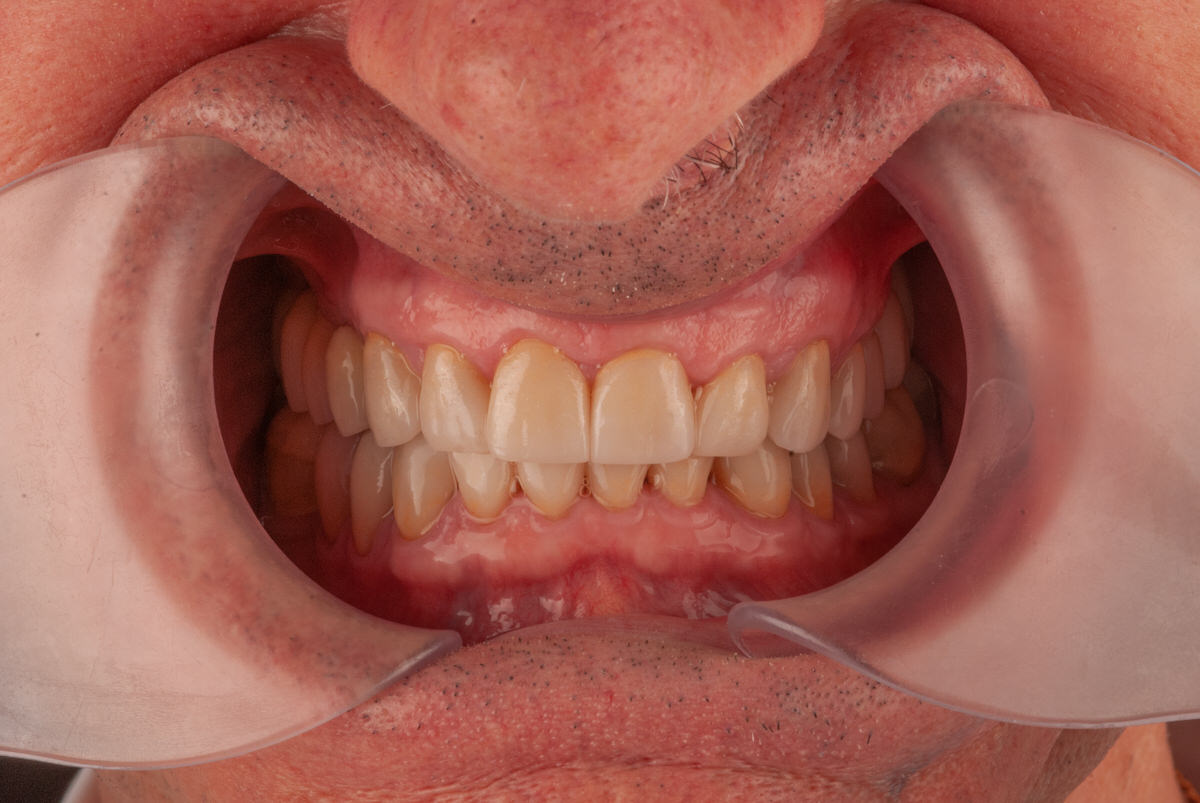

Plan de Tratamiento para el Bruxismo

1. Restauración de Volumen y Altura: Devolvimos el volumen perdido a los dientes y restauramos la altura de la mordida colapsada.

2. Rehabilitación Mínimamente Invasiva: El tratamiento fue diseñado para ser lo menos invasivo posible, añadiendo material donde el paciente había perdido esmalte sin desgastar más sus dientes.

En solo cuatro visitas, logramos una rehabilitación completa con resultados excepcionales. La sonrisa del paciente mejoró significativamente y, lo más importante, el tratamiento se mantuvo estable a lo largo del tiempo, brindando una solución duradera al problema del bruxismo.